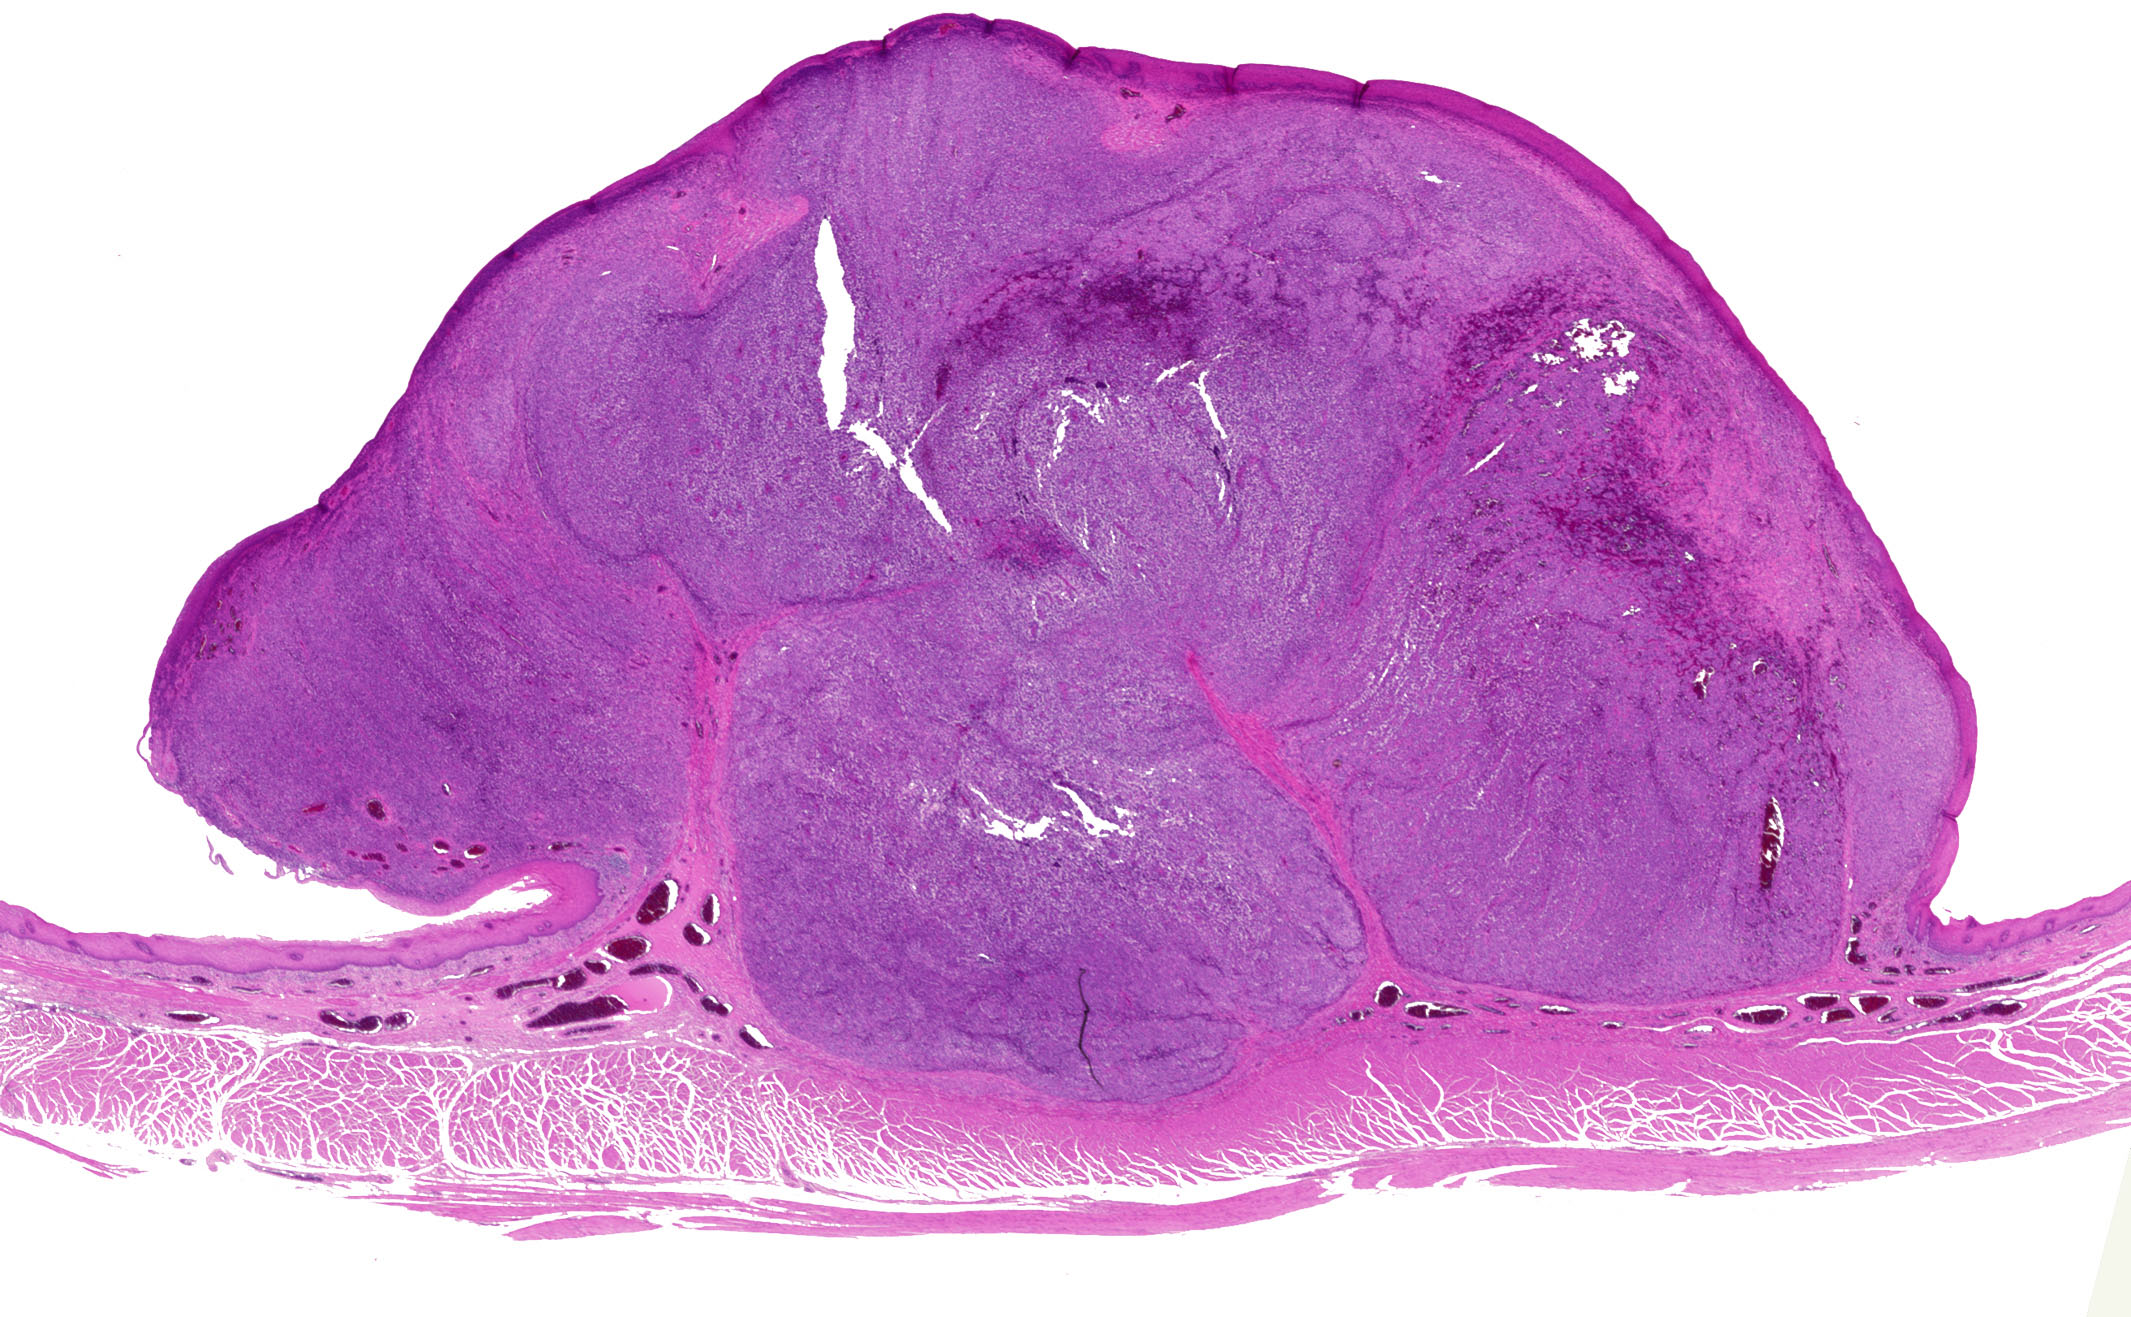

Microscopic (histologic) images

- Associated melanoma in situ component (junctional melanocytic activity / junctional melanocytic component / tumor nests at the epithelium - lamina propria junction / horizontal tumor spread in the basal layer of the epithelium) and melanocytosis / melanosis (Mod Pathol 2019;32:957, Ann Thorac Surg 2013;96:1002)

Microscopic (histologic) description